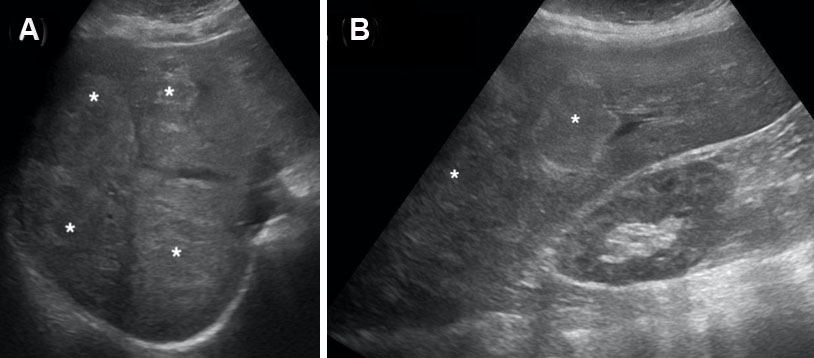

Figure 10: Hepatocellular carcinoma (*) with adjacent scanty viable liver tissue (arrow) (H&E stain, 100× magnification).

Share Image:

Figure 11: Viable Hepatocellular carcinoma (*) with extensive necrosis (arrow) (H&E stain, 100× magnification).